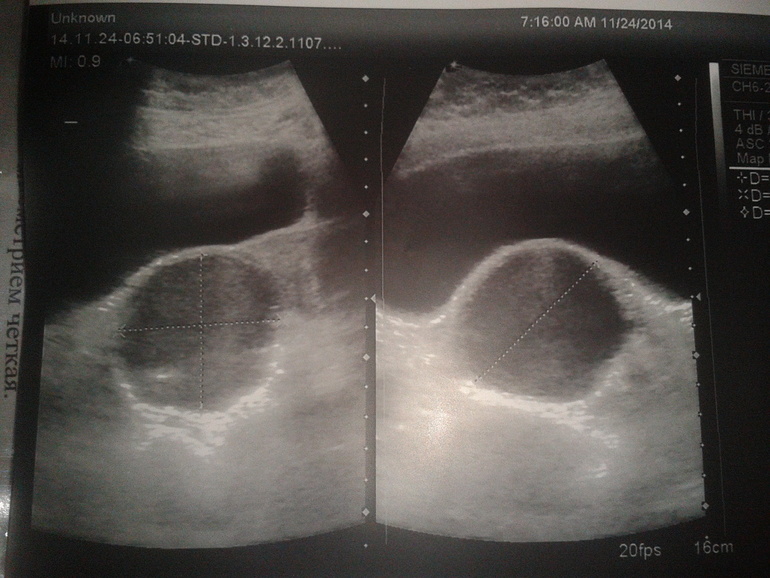

сходила тут на узи, но только поверхностное и просто в шоке.... ушла никакая. шла за одним, а получила.... на фото... неужели это оно?? посмотрите пожалуйста

врач не мог рассмотреть левый яичник и так давил, что я чуть глаза наружу... потом аж двумя руками и все таки увидела, что он аж смешено. наверху мочевой пузырь, а вот шарик.... сказала, что киста правого яичника. как приговор для меня! хотя что-то говорила про ЖТ, но как-то не понятно. и очень удивилась, а зачем я БТ меряю.

хотя до этого видела на форуме похожее фото и там у девушки это ЖТ, а вдруг это не оно?